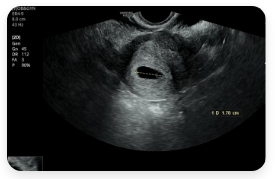

- 생리 지연 후 임신 테스트 양성

- 입덧, 임신 초기 출혈

- 태아 초음파, 정기적인 산전검사

- 고위험 임신 (당뇨, 고혈압 등)

- 출산 상담, 제왕절개 계획